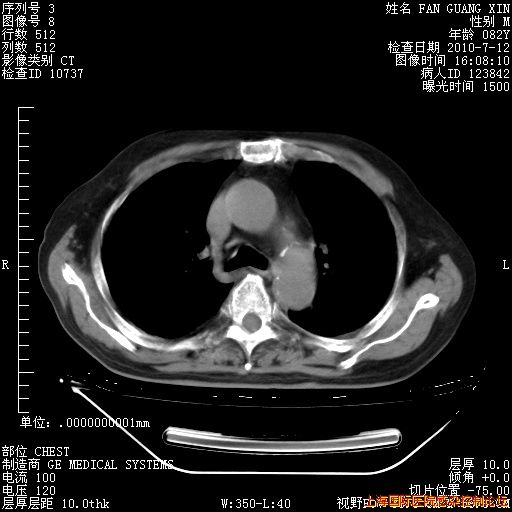

今天复查CT